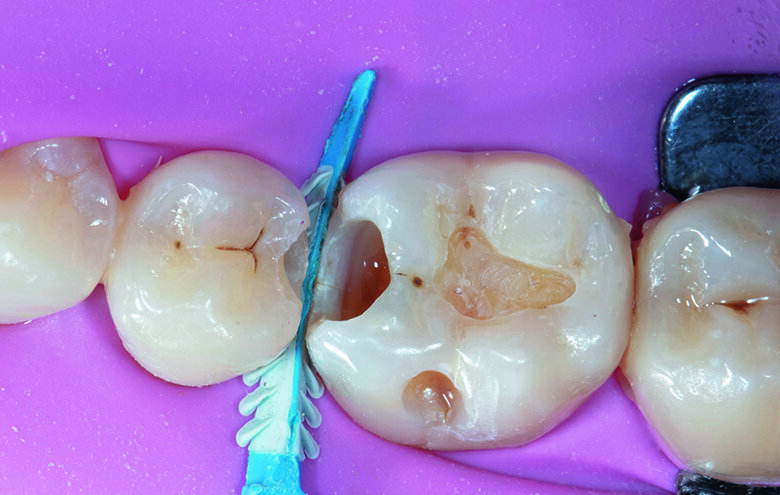

To restore the Class II cavity of tooth #46, a combination of vertical, horizontal and oblique layering technique was adopted. A thin layer of Beautifil Injectable XSL (Self-leveling composite resin) shade A2 was first injected and spread in the proximal box area and light cured to ensure a complete seal (Fig. 6).

Followed by the proximal wall and marginal ridge build-up with Beautifil II LS shade A2 to convert the original Class II into a Class I cavity. Once the proximal wall and contact was achieved the matrix band and ring were removed (Fig. 7).